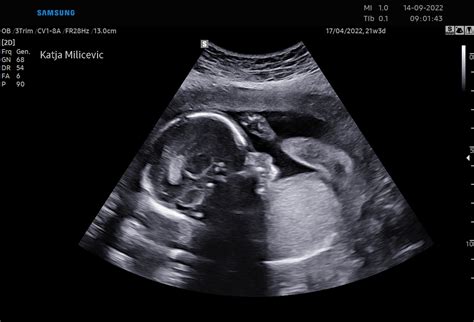

Nuhalna svetlina in hormonski testi, ki se običajno opravijo med 11. in 13. tednom nosečnosti, so že za vami. Pred vami je ključni pregled, ki ga imenujejo "morfologija", običajno okoli 20. tedna nosečnosti, kjer se podrobno pregledajo različni deli telesa ploda.

- 15.-16. teden: Plod meri okoli 10 cm in tehta okoli 70 g. Lahko sesa svoj palec. Kosti se krepijo, mišice se razvijajo. Oči so dovzetne za svetlobo, razvija se sluh. Od 16. tedna je možna amniocenteza.

- 19.-20. teden: Možgani se intenzivno razvijajo, rast ploda se nadaljuje. Morda prvič občutite gibe ploda. Opravi se morfološki ultrazvočni pregled. Na koži se pojavi zaščitna snov - verniks.